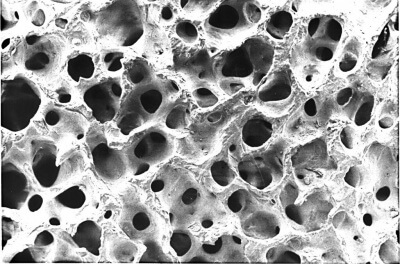

- Свойства препаратов которые Мы используем в качестве имплантатов. Их резорбция и способность к остеоиндукции и остеокондукции.

![IMG_2280[1]](http://www.bioimplantat.ru/wp-content/uploads/IMG_22801.jpg) Чем больше соприкосновение биопластического материала с костью и богаче кровоснабжение - тем больше кости Вы получите. Резорбируемые коллагеновые мембраны, такие как Биоматрикс мембрана, в процессе их физиологической реконструкции трансформируются в грубоволокнистую фиброзную ткань, которая формирует дополнительный и надежный барьер между аугментатом и полостью носа.

Чем больше соприкосновение биопластического материала с костью и богаче кровоснабжение - тем больше кости Вы получите. Резорбируемые коллагеновые мембраны, такие как Биоматрикс мембрана, в процессе их физиологической реконструкции трансформируются в грубоволокнистую фиброзную ткань, которая формирует дополнительный и надежный барьер между аугментатом и полостью носа.

Далее мы рекомендуем укладывать Остеоматрикс в виде чипсов. Это остеоиндуктивный материал, который непосредственно участвует в стимуляции процессов костеобразования и в дальнейшем полностью замещается вновь образованной костью (рис 5).

Далее мы рекомендуем укладывать Остеоматрикс в виде чипсов. Это остеоиндуктивный материал, который непосредственно участвует в стимуляции процессов костеобразования и в дальнейшем полностью замещается вновь образованной костью (рис 5).